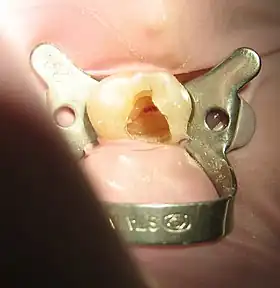

![]() Tooth #13, the upper left second premolar, after excavation of DO decay. There was a carious exposure into the pulp chamber (red oval), and the photo was taken after endodontic access was initiated and the roof of the chamber was removed. | |

Isolating the tooth

The use of a rubber dam for tooth isolation is mandatory in endodontic treatment for several reasons:

- It provides an aseptic operating field, isolating the tooth from oral and salivary contamination. Root canal contamination with saliva introduces new microorganisms to the root canal which compromise the prognosis.

- It facilitates the use of the strong medicaments necessary to clean the root canal system.

- It protects the patient from the inhalation or ingestion of endodontic instruments.